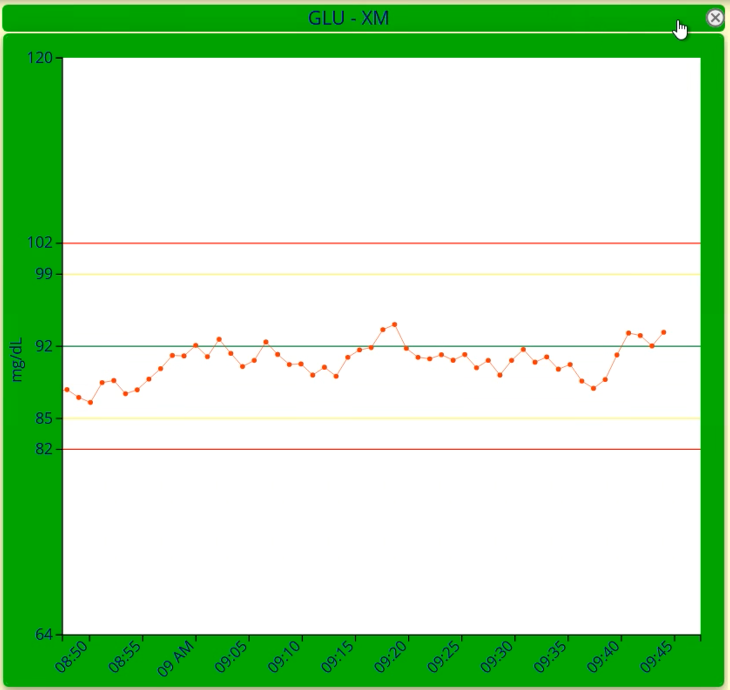

Moving Averages & Moving Medians

Available as an integrated IM module, our popular Moving Averages & Moving Medians app is now better than ever with Instrument Manager 9.01.

Stay one step ahead of quality issues. Detect deviations in instrument performance before they jeopardize patient results and require result rework. With IM 9.01, Moving Averages has been modernized with upgraded technology and an improved user experience to make laboratory quality tracking easier than ever.